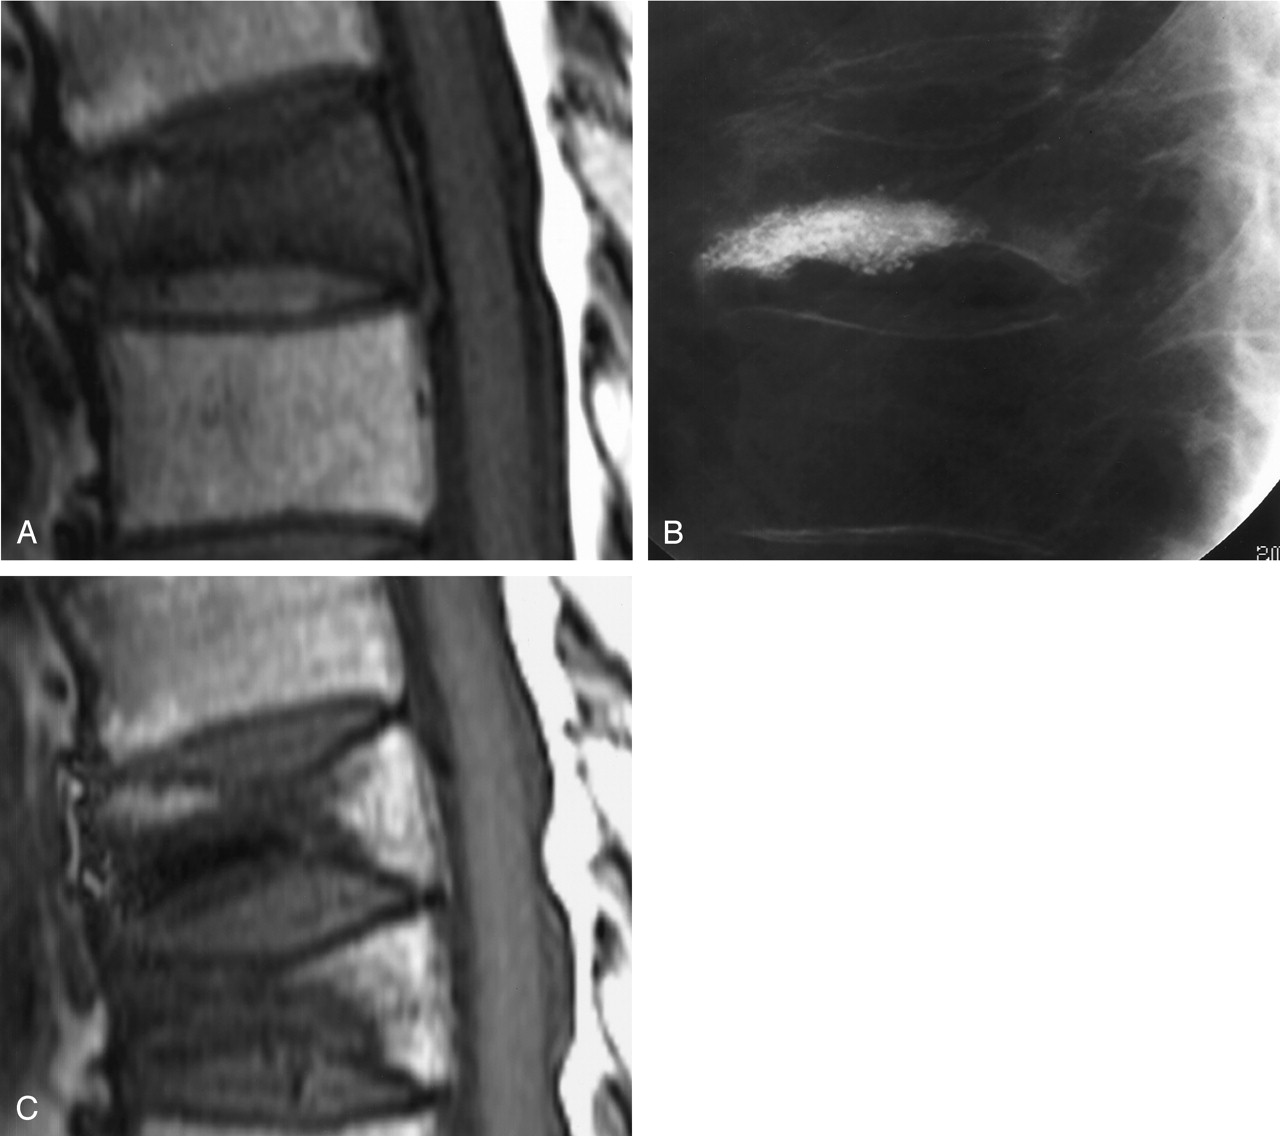

Additional height loss after VP.

A, T1-weighted MRI before L1 VP shows vertebral compression and marrow edema.

B, VP shows cement extending between the endplates of L1.

C, Follow-up T1-weighted MRI shows further vertebral compression primarily involving the anterior and middle aspects of the L1 body.

Height loss was assessed quantitatively and by consensus opinion. Nine (18%) of 51 treated vertebrae lost additional height between the VP conventional radiographs and the follow-up MRI (Fig 1). In a single additional case, a compressed vertebra lost height between the preoperative MRI and the VP.

On preoperative MRI, the 51 untreated vertebral fractures had lost an average of 34% (range, 10%–80%; median, 30%) of their original height. In the nine vertebrae that lost additional height after the VP, the average vertebral height loss on follow-up MRI was 50% (range, 20%–80%; median, 50%). When these vertebrae were re-evaluated by using the midline sagittal image measurements, the average preoperative mean height was 16.0 mm (three midline sagittal measurements averaged for each vertebra), and the average interval height loss was 1.2 mm (8%). In many instances, the additional height loss involved only one part of the vertebral body. When only the single measurement of maximum difference (anterior, middle, or posterior) from the midline sagittal MRI image was considered, the average interval height loss was 2.2 mm (14%).